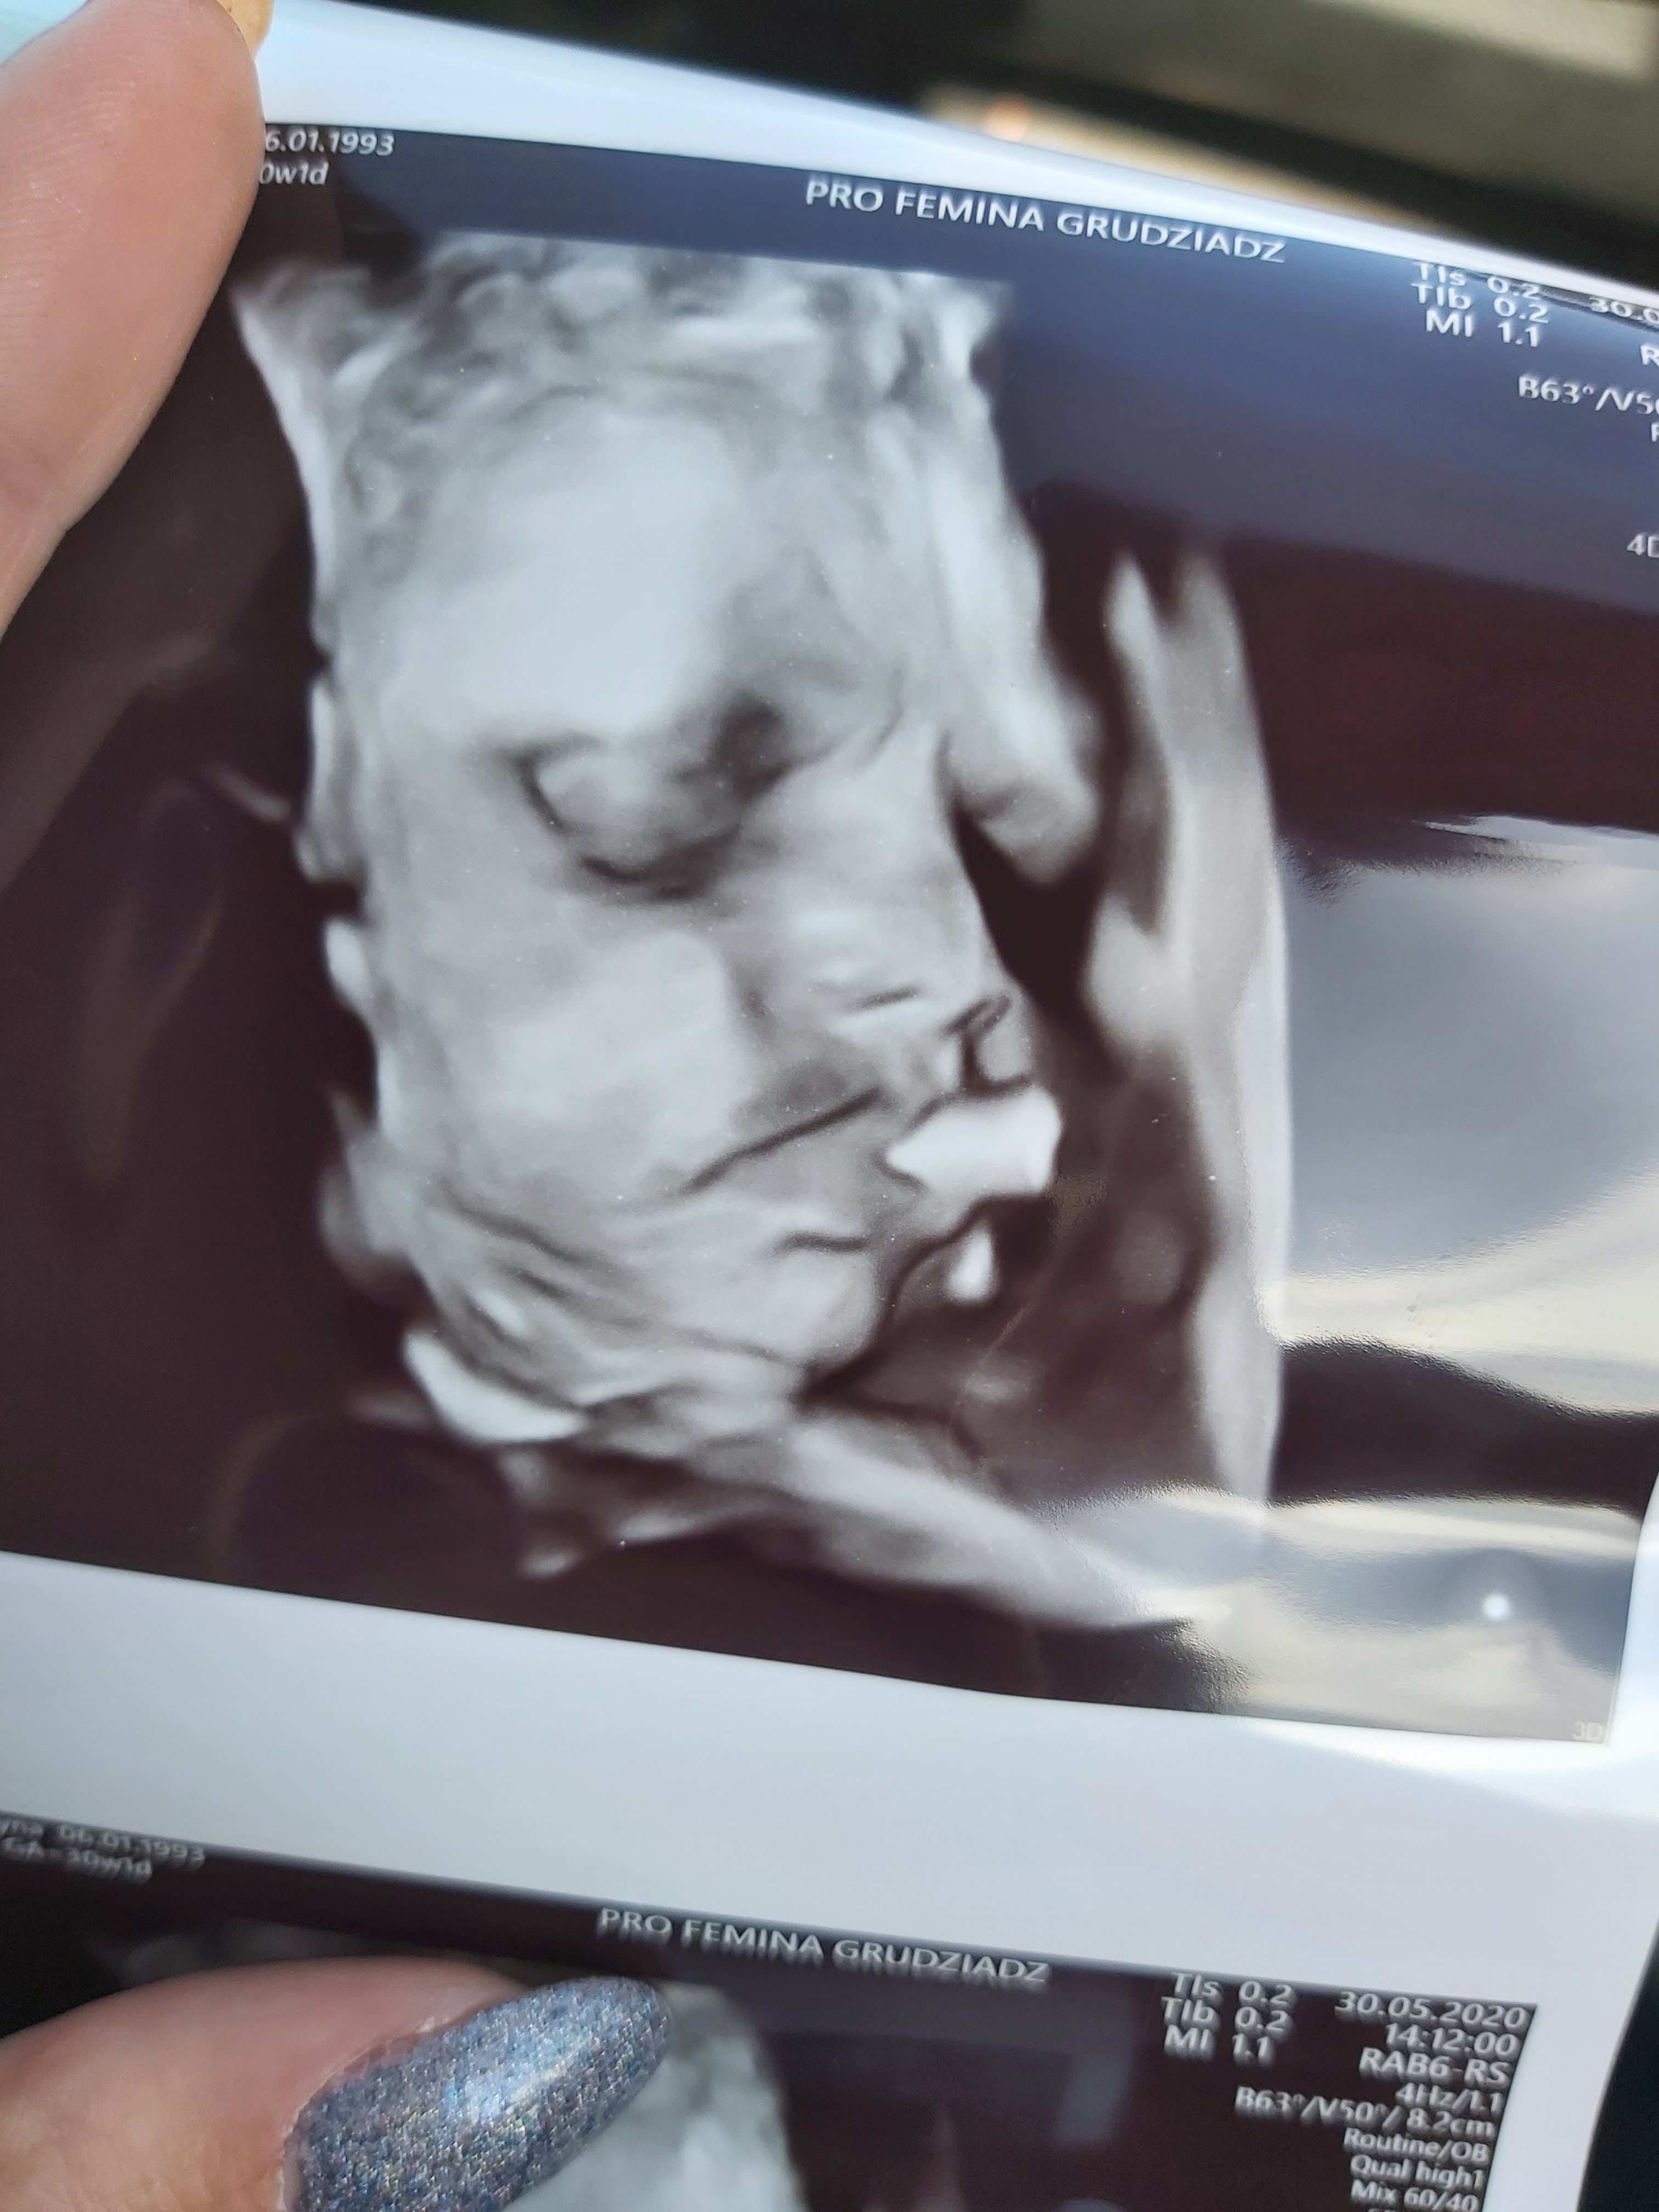

Patrycja piękne zdjęcia. I szczególne gratulacje